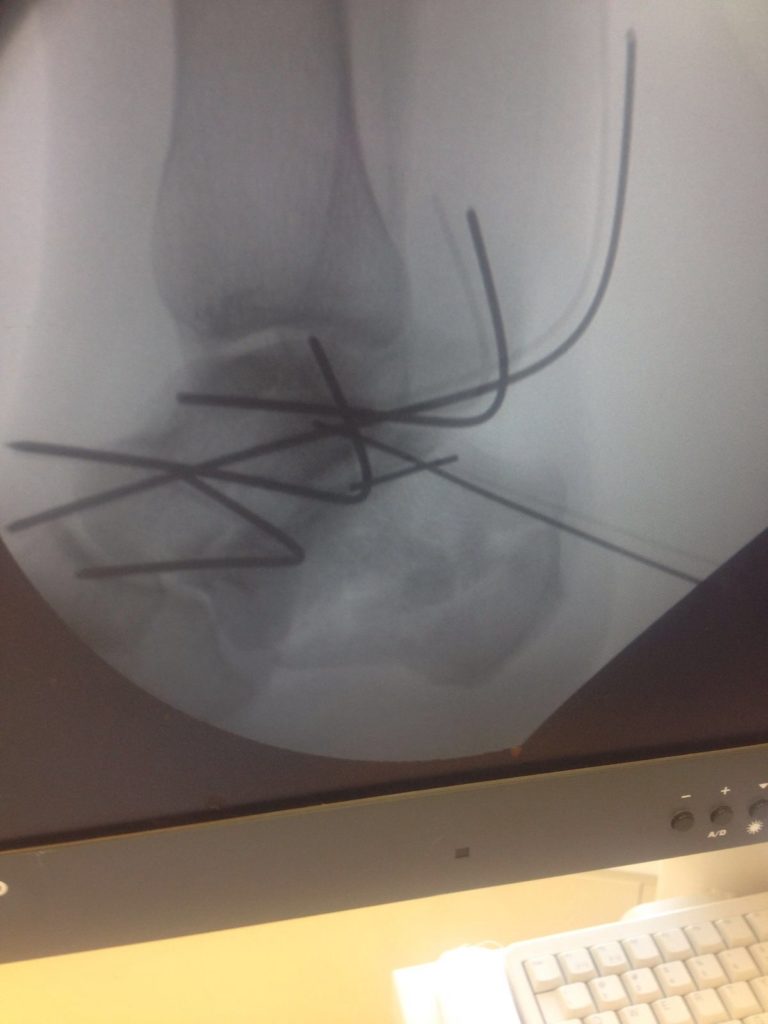

Операция – открытая репозиция, остеосинтез пяточной кости пластиной с костной ксенопластикой материалом «Остеоматрикс». На контрольных снимках в три месяца имеется консолидация перелома, миграции фиксатора нет, имеется остеоинтеграция ксенопластического материала.

Отдаленные результаты через 6 (шесть) месяцев: